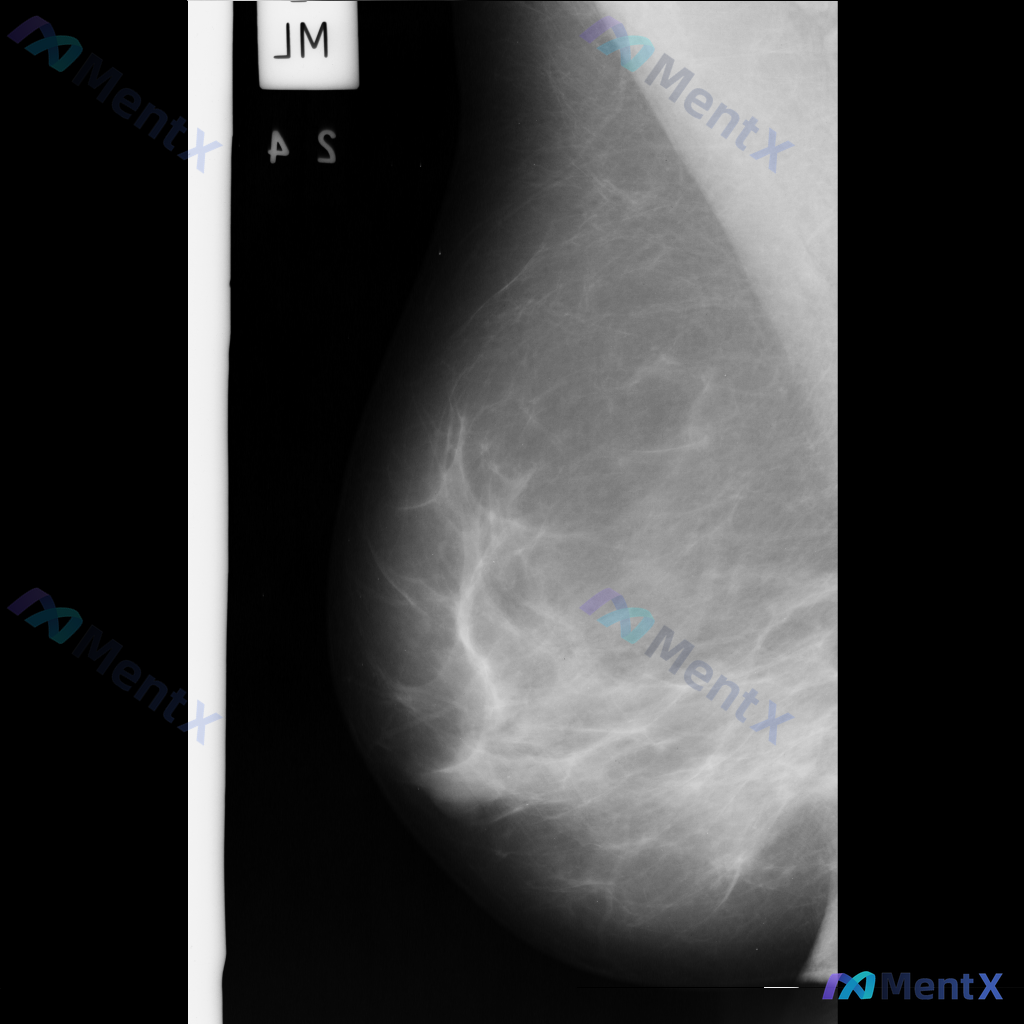

整理到一张乳腺钼靶影像资料,目前只有单张图像,没有提供双侧对比和多体位视图。 从这张图像来看,主要表现是腺体组织与脂肪组织混合存在,腺体分布相对广泛。目前没有看到非常明确的肿块、成簇钙化或明显的结构扭曲这类表现。 想跟大家讨论一下,单看目前这张影像,大家会优先考虑哪一种情况?另外,对于这类单张图像的...

整理到一份右侧乳腺内外斜位钼靶X光片的影像资料,大家可以一起讨论下: - 影像中可见散在的纤维腺体密度,密度较高 - 发现多发斑点状或细小钙化点,分布散在,目前倾向良性特征 - 另有局部模糊的不对称致密影,与背景腺体组织融合,未见明确毛刺或结构扭曲等恶性特征 单看这份影像描述,大家会优先考虑什么方向...